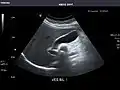

Left kidney

Kidneys: Right and left kidneys measure 11.5 cm and 12 cm in length respectively. No hydronephrosis. Small left lower pole kidney cyst.